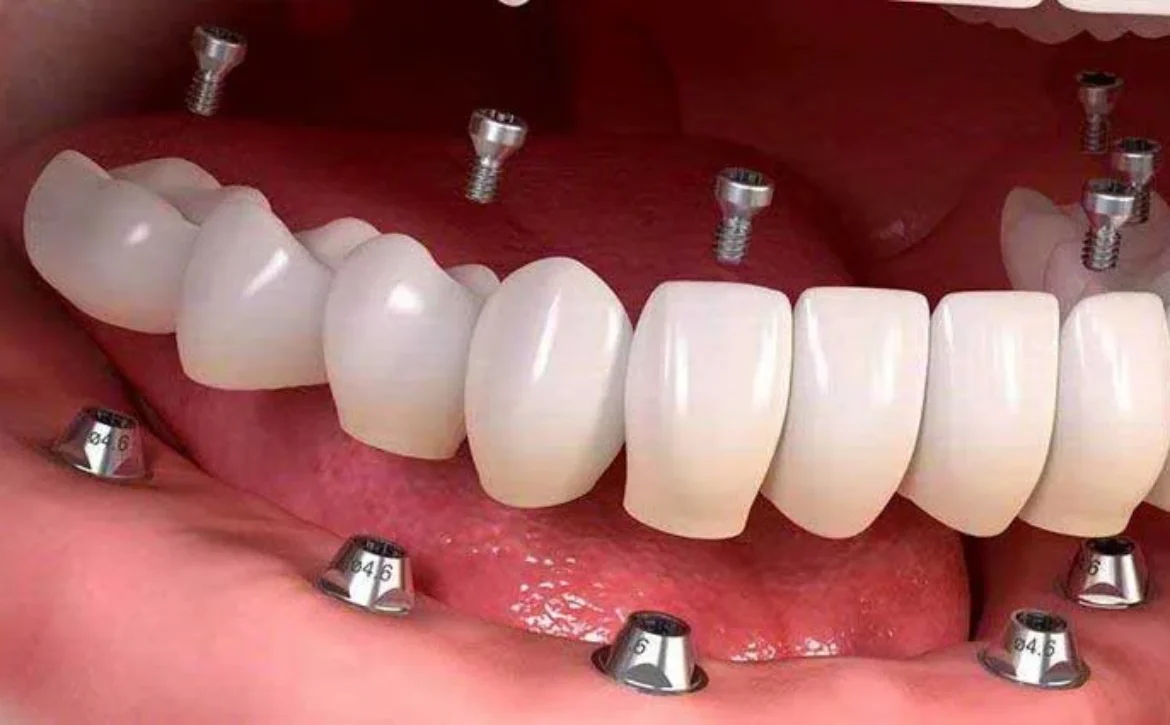

ایمپلنت‌ها بسته به نیاز بیمار و شرایط دهان و فک در انواع مختلفی ارائه می‌شوند.

مدل تک‌دندانی برای جایگزینی یک دندان از دست‌رفته استفاده می‌شود.

کاشت ایمپلنت چندتایی زمانی کاربرد دارد که چند دندان مجاور از دست رفته باشند.

ایمپلنت کامل فک برای بیمارانی مناسب است که تمام دندان‌های یک فک را از دست داده‌اند. ایمپلنت فوری نیز گزینه‌ای است که تاج دندان بلافاصله پس از قرار دادن پایه نصب می‌شود و زمان درمان را کاهش می‌دهد.

پروتز متکی بر ایمپلنت ترکیبی از فناوری ایمپلنت و پروتز متحرک است که ثبات بیشتری دارد و بیمار احساس راحتی بیشتری خواهد داشت. این نوع پروتز به کمک چند پایه ایمپلنت در فک ثابت می‌شود و مانع از لغزش یا جابجایی آن در دهان می‌گردد.